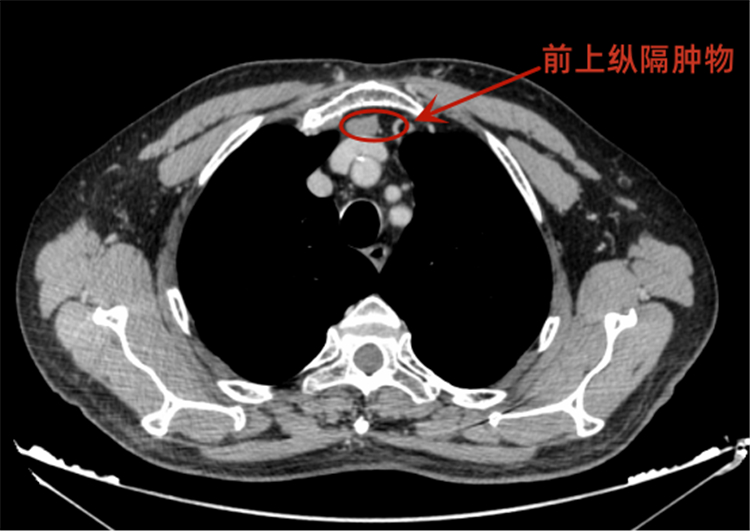

近期,72岁的患者尹先生(化名)在体检中发现前上纵隔存在肿物,随后前往长沙泰和医院胸外科就诊。接诊的胸外科首席专家周勇教授详细查看其胸部增强CT影像后,发现肿瘤位置紧邻重要血管,且胸骨后空间狭窄,若采用传统手术入路,视野受限,操作风险较高。